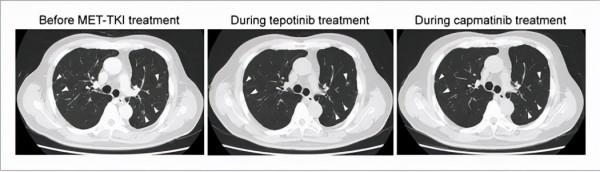

圖注:採用MET TKI前的一系列胸部CT影象顯示多發性肺轉移灶(白色箭頭),Tepotinib治療使得這些轉移灶縮小,在卡馬替尼治療期間維持了這種縮小。